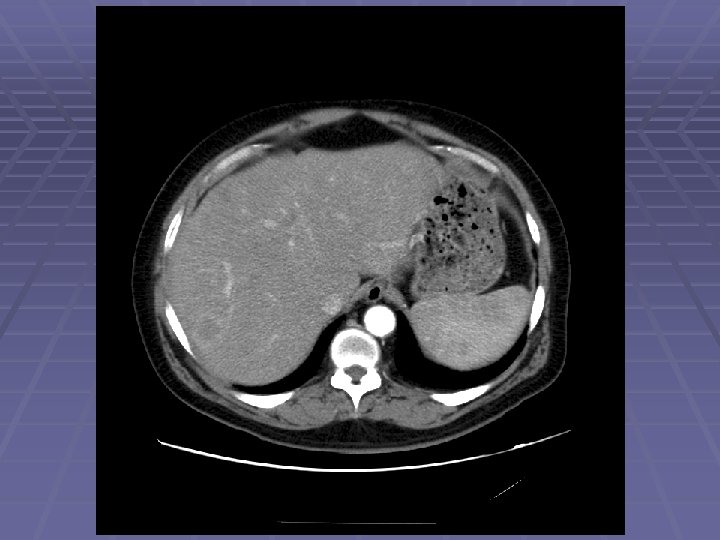

EUS Evaluation of Left Lobe of Liver